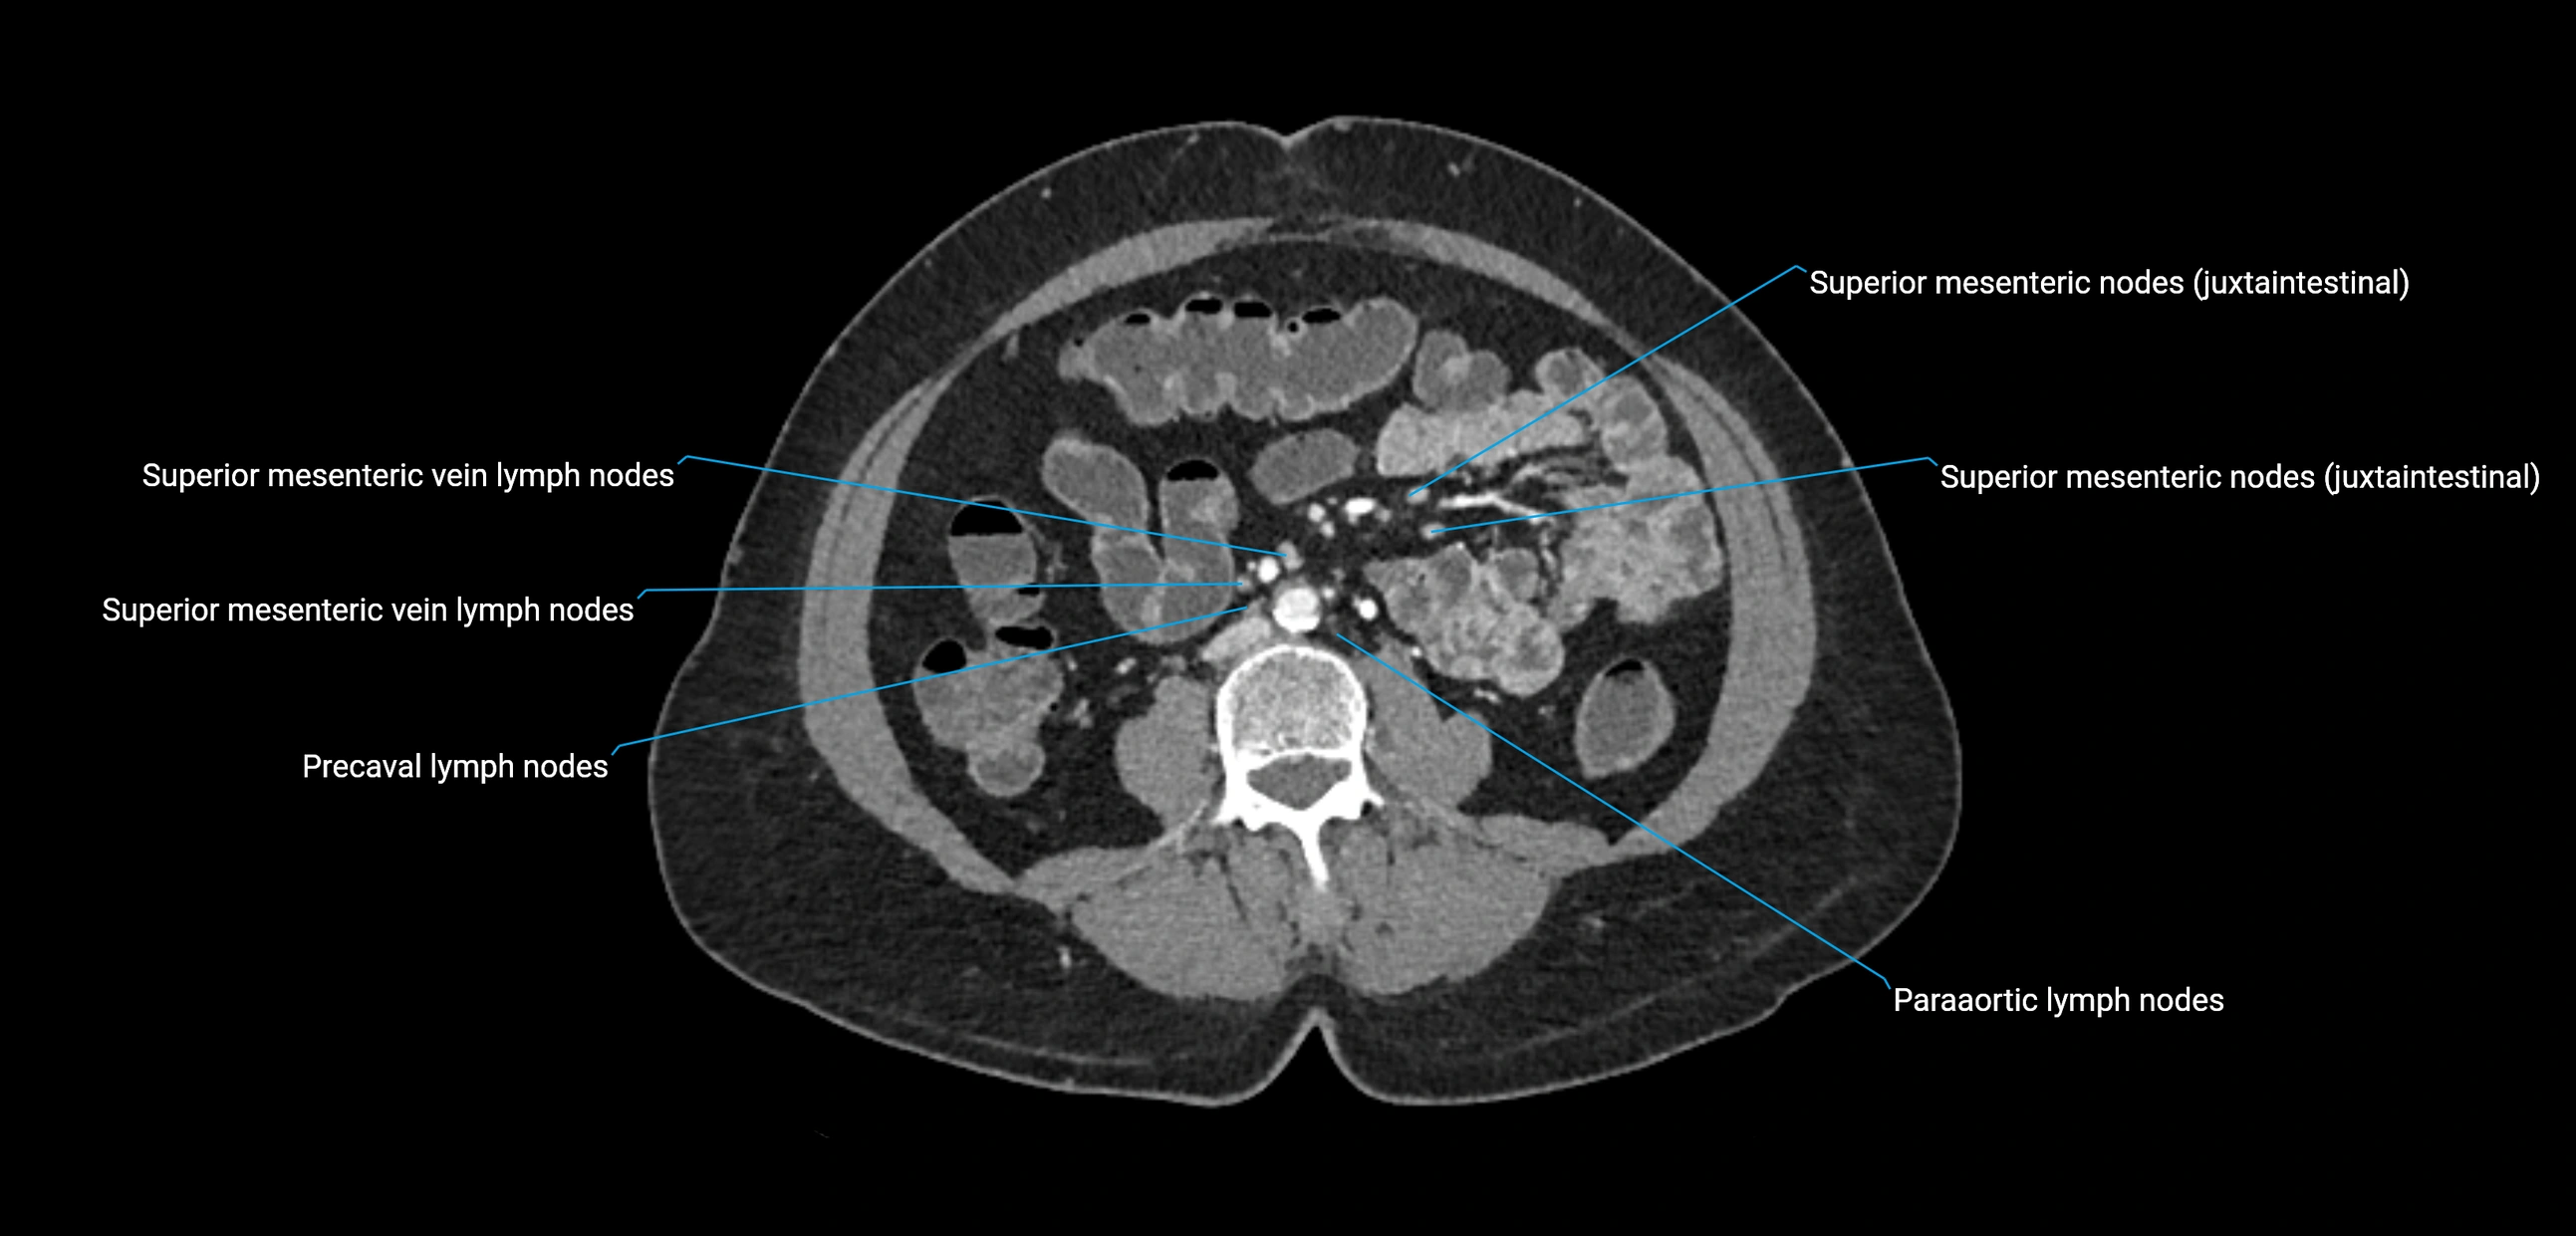

CT Appearance

CT Pre-Contrast:

• Nodes appear as soft-tissue density nodules adjacent to the aorta and IVC

• Calcification may be seen in chronic infections (e.g., tuberculosis)

CT Post-Contrast:

• Normal nodes enhance homogeneously

• Malignant nodes may show heterogeneous enhancement, central necrosis, or conglomerate formation

• Size >1 cm short axis is suspicious, though morphology and distribution are equally important